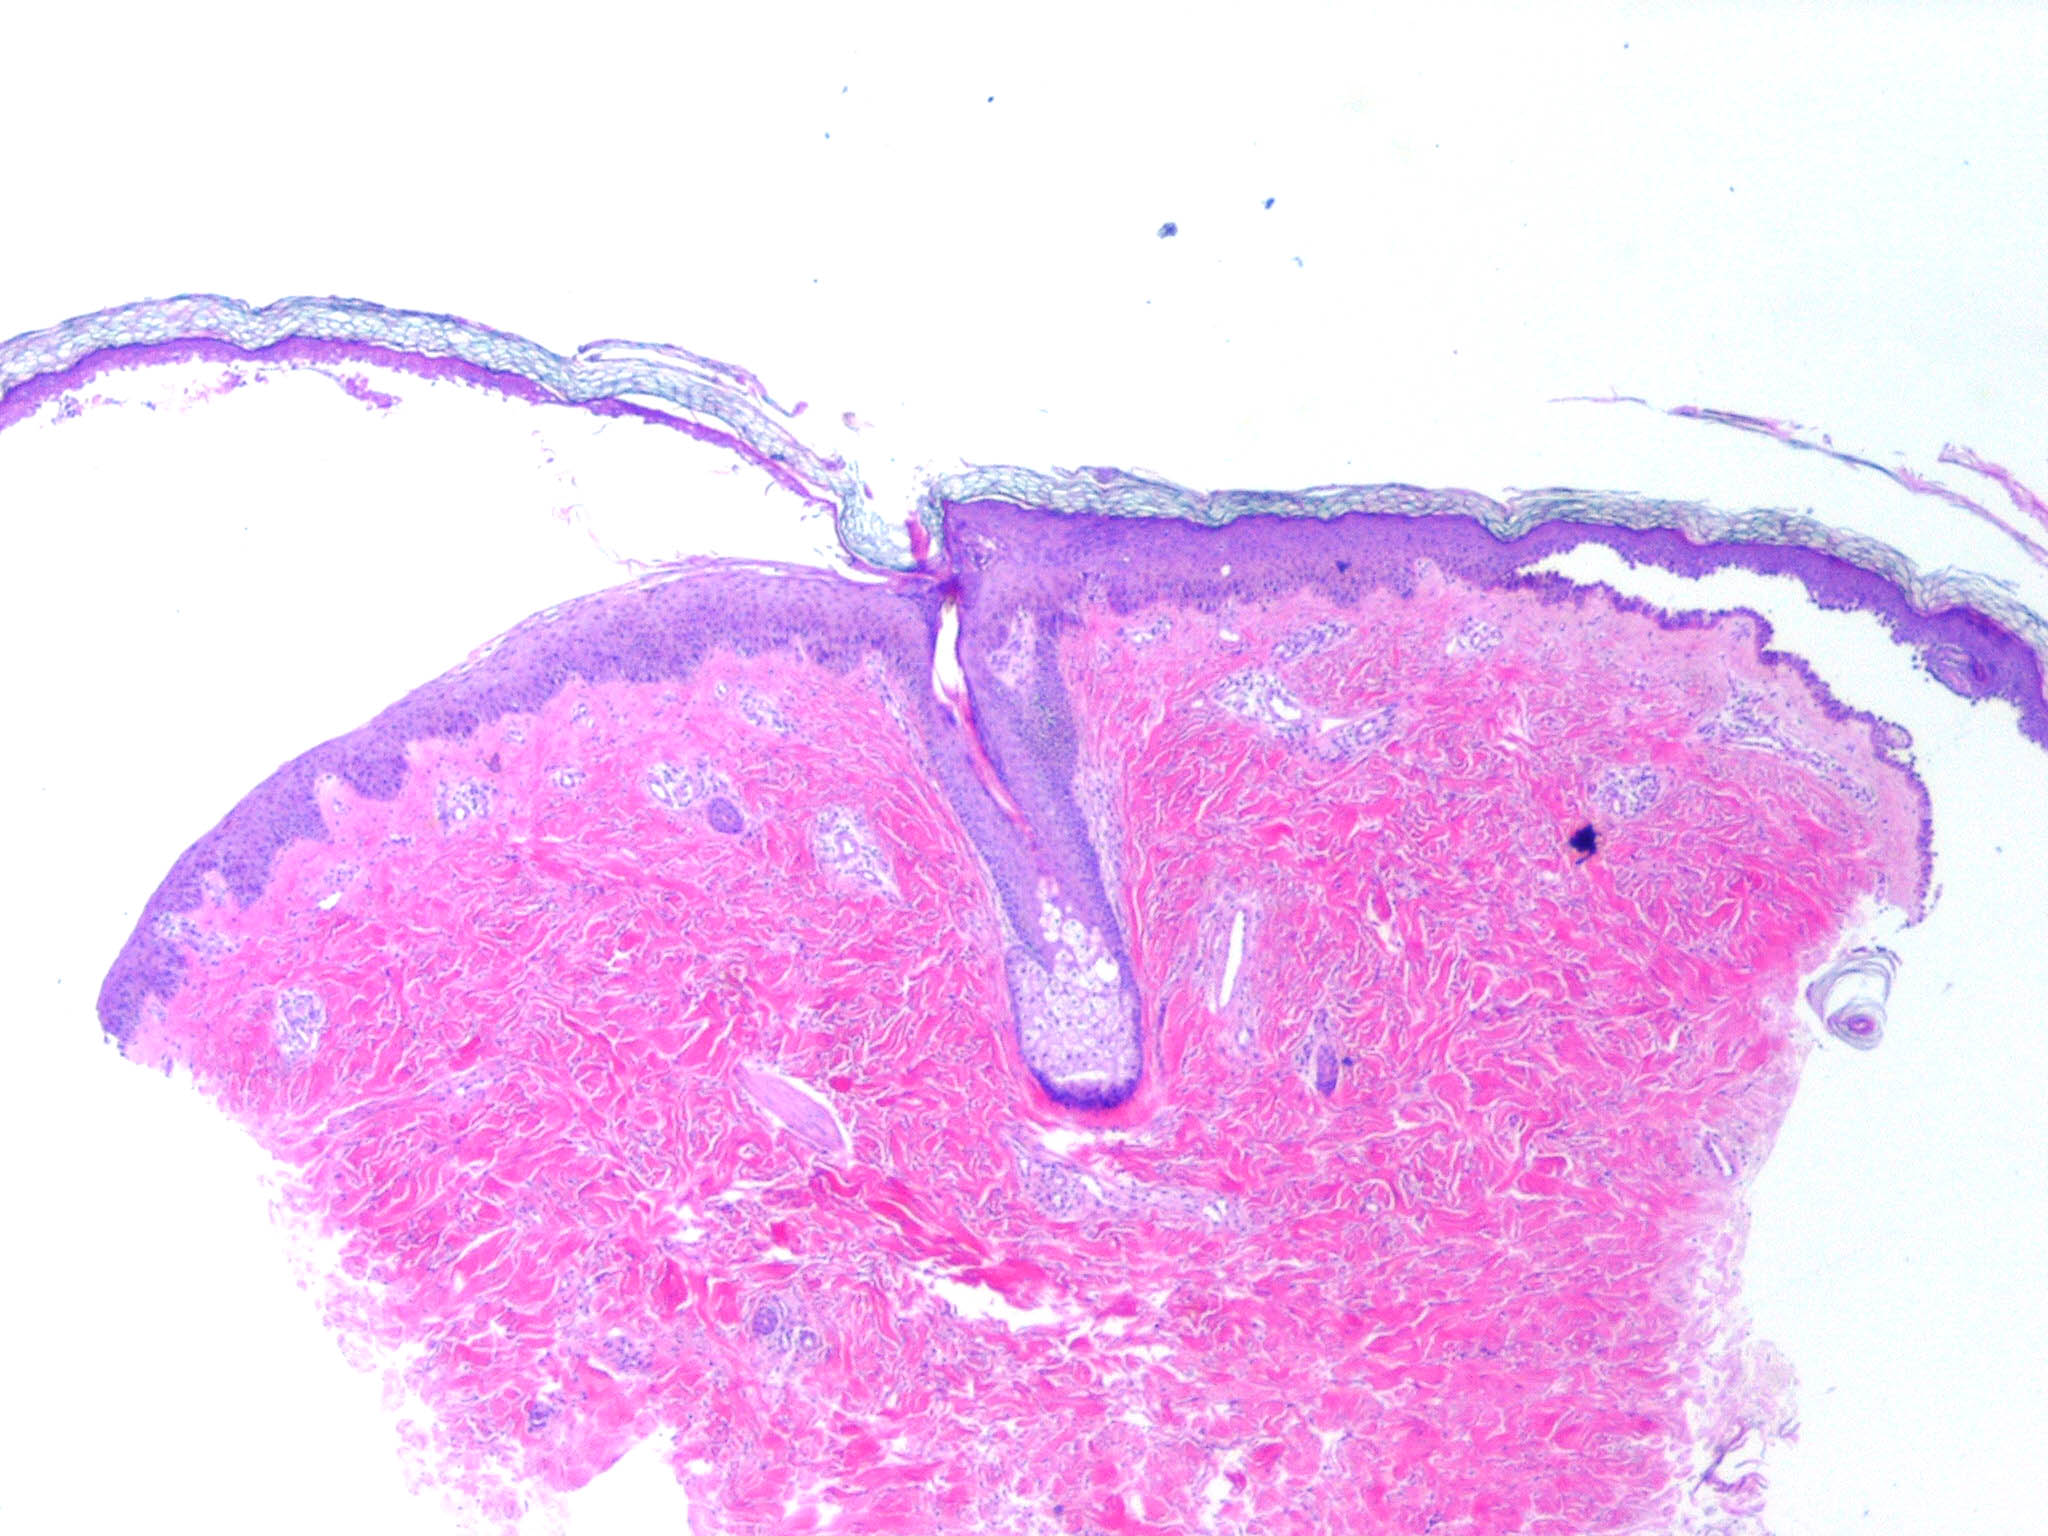

The earliest recognized change may be either eosinophilic spongiosis rarely or, more commonly, “spongiosis” in the lower epidermis . This spongiosis may actually represent the earliest manifestation of acantholysis rather than true spongiosis as defined earlier. Acantholysis leads first to the formation of clefts and then to blisters in a predominantly suprabasallocation . The intraepithelial acantholysis may extend into adnexal structures or occasionally be higher in the stratum spinosum. The basal keratinocytes, although separated from one another through the loss of attachment, remain firmly attached to the dermis like a “row of tombstones.” Within the blister cavity, the acantholytic keratinocytes, singularly or in clusters, have rounded condensed cytoplasm about an enlarged nucleus with peripherally palisaded chromatin and enlarged nucleoli. In some patients, there are varying quantities of antidesmoglein 1 and antidesmoglein 3 antibodies, leading to variable planes of acantholysis. There is little inflammation in the early phase of blister formation. If present, it is usually a sparse, lymphocytic perivascular infiltrate accompanied by dermal edema. However, if eosinophilic spongiosis is apparent, numerous eosinophils may infiltrate the dermis. The phenomenon of eosinophilic spongiosis occurs occasionally in other blistering diseases, particularly in their early phases, including acute contact dermatitis, pemphigus foliaceus, bullous pemphigoid, herpes gestation is, drug eruptions, spongiotic arthropod bite reactions, and transient acantholytic dermatosis. Several important changes ensue as the lesions age. First, a mixed inflammatory cell reaction consisting of neutrophils, lymphocytes, macrophages, and eosinophils may develop. Because of the instability of the blister roof, erosion and ulceration may occur. Older blisters may also have several layers of keratinocytes at the blister base because of keratinocyte migration and proliferation. Last, there may be considerable downward growth of epidermal strands, giving rise to so-called villi (Fig. 9-9D). The evaluation of patients with only oral lesions is difficult, because intact blisters are rarely encountered due to the trauma of mastication, and biopsies may show only erosion and ulceration. Indeed, it is best to sample the edge of a denuded area with intact mucosa in an attempt to demonstrate the typical pathologic changes. Clinicians frequently cannot distinguish between an ulcer and the intact mucosa, as both are often white and shaggy. In patients with only oral lesions, biopsies of intact oral mucosa for DIF testing are more sensitive than biopsies of lesions for routine light microscopic evaluation. Therefore, biopsy from the normal maxillary and upper buccal mucosa is necessary when there is extensive ulceration. Cytologic examination using a Tzanck preparation is useful for the rapid demonstration of acantholytic epidermal keratinocytes in the blisters of pemphigus vulgaris. For this